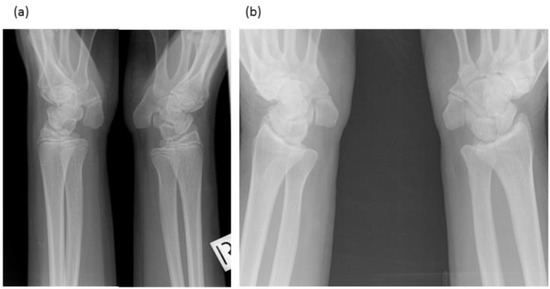

3.1.1. Female Proband (IV-12)

3.1.2. Brother (IV-10)

3.1.3. Brother (IV-9)

3.1.4. Male Cousin (IV-5)

| Proband (IV-12) | F | 0–27 | Carpal Tarsal Coalition, Pisiform elongated No hearing impairment or congenital vertebral fusion, Postnatal vertebral fusion, speech impaired, short tongue and microstomia. |

| Brother (IV-10) | M | 7–26 | Carpal Tarsal Coalition, Pisiform elongated No hearing impairment or congenital vertebral fusion, Postnatal vertebral fusion, No speech impairment, short tongue and microstomia. |

| Brother (IV-9) | M | 12–19 | Carpal Tarsal Coalition, Pisiform elongated No hearing impairment, Postnatal vertebral fusion, Severe speech impairment, short tongue and microstomia. |

| Cousin (IV-5) | M | 17–50 | Carpal Tarsal Coalition, Pisiform not tested No hearing impairment, Progressive vertebral fusion, Severe speech impairment, short tongue and microstomia. |